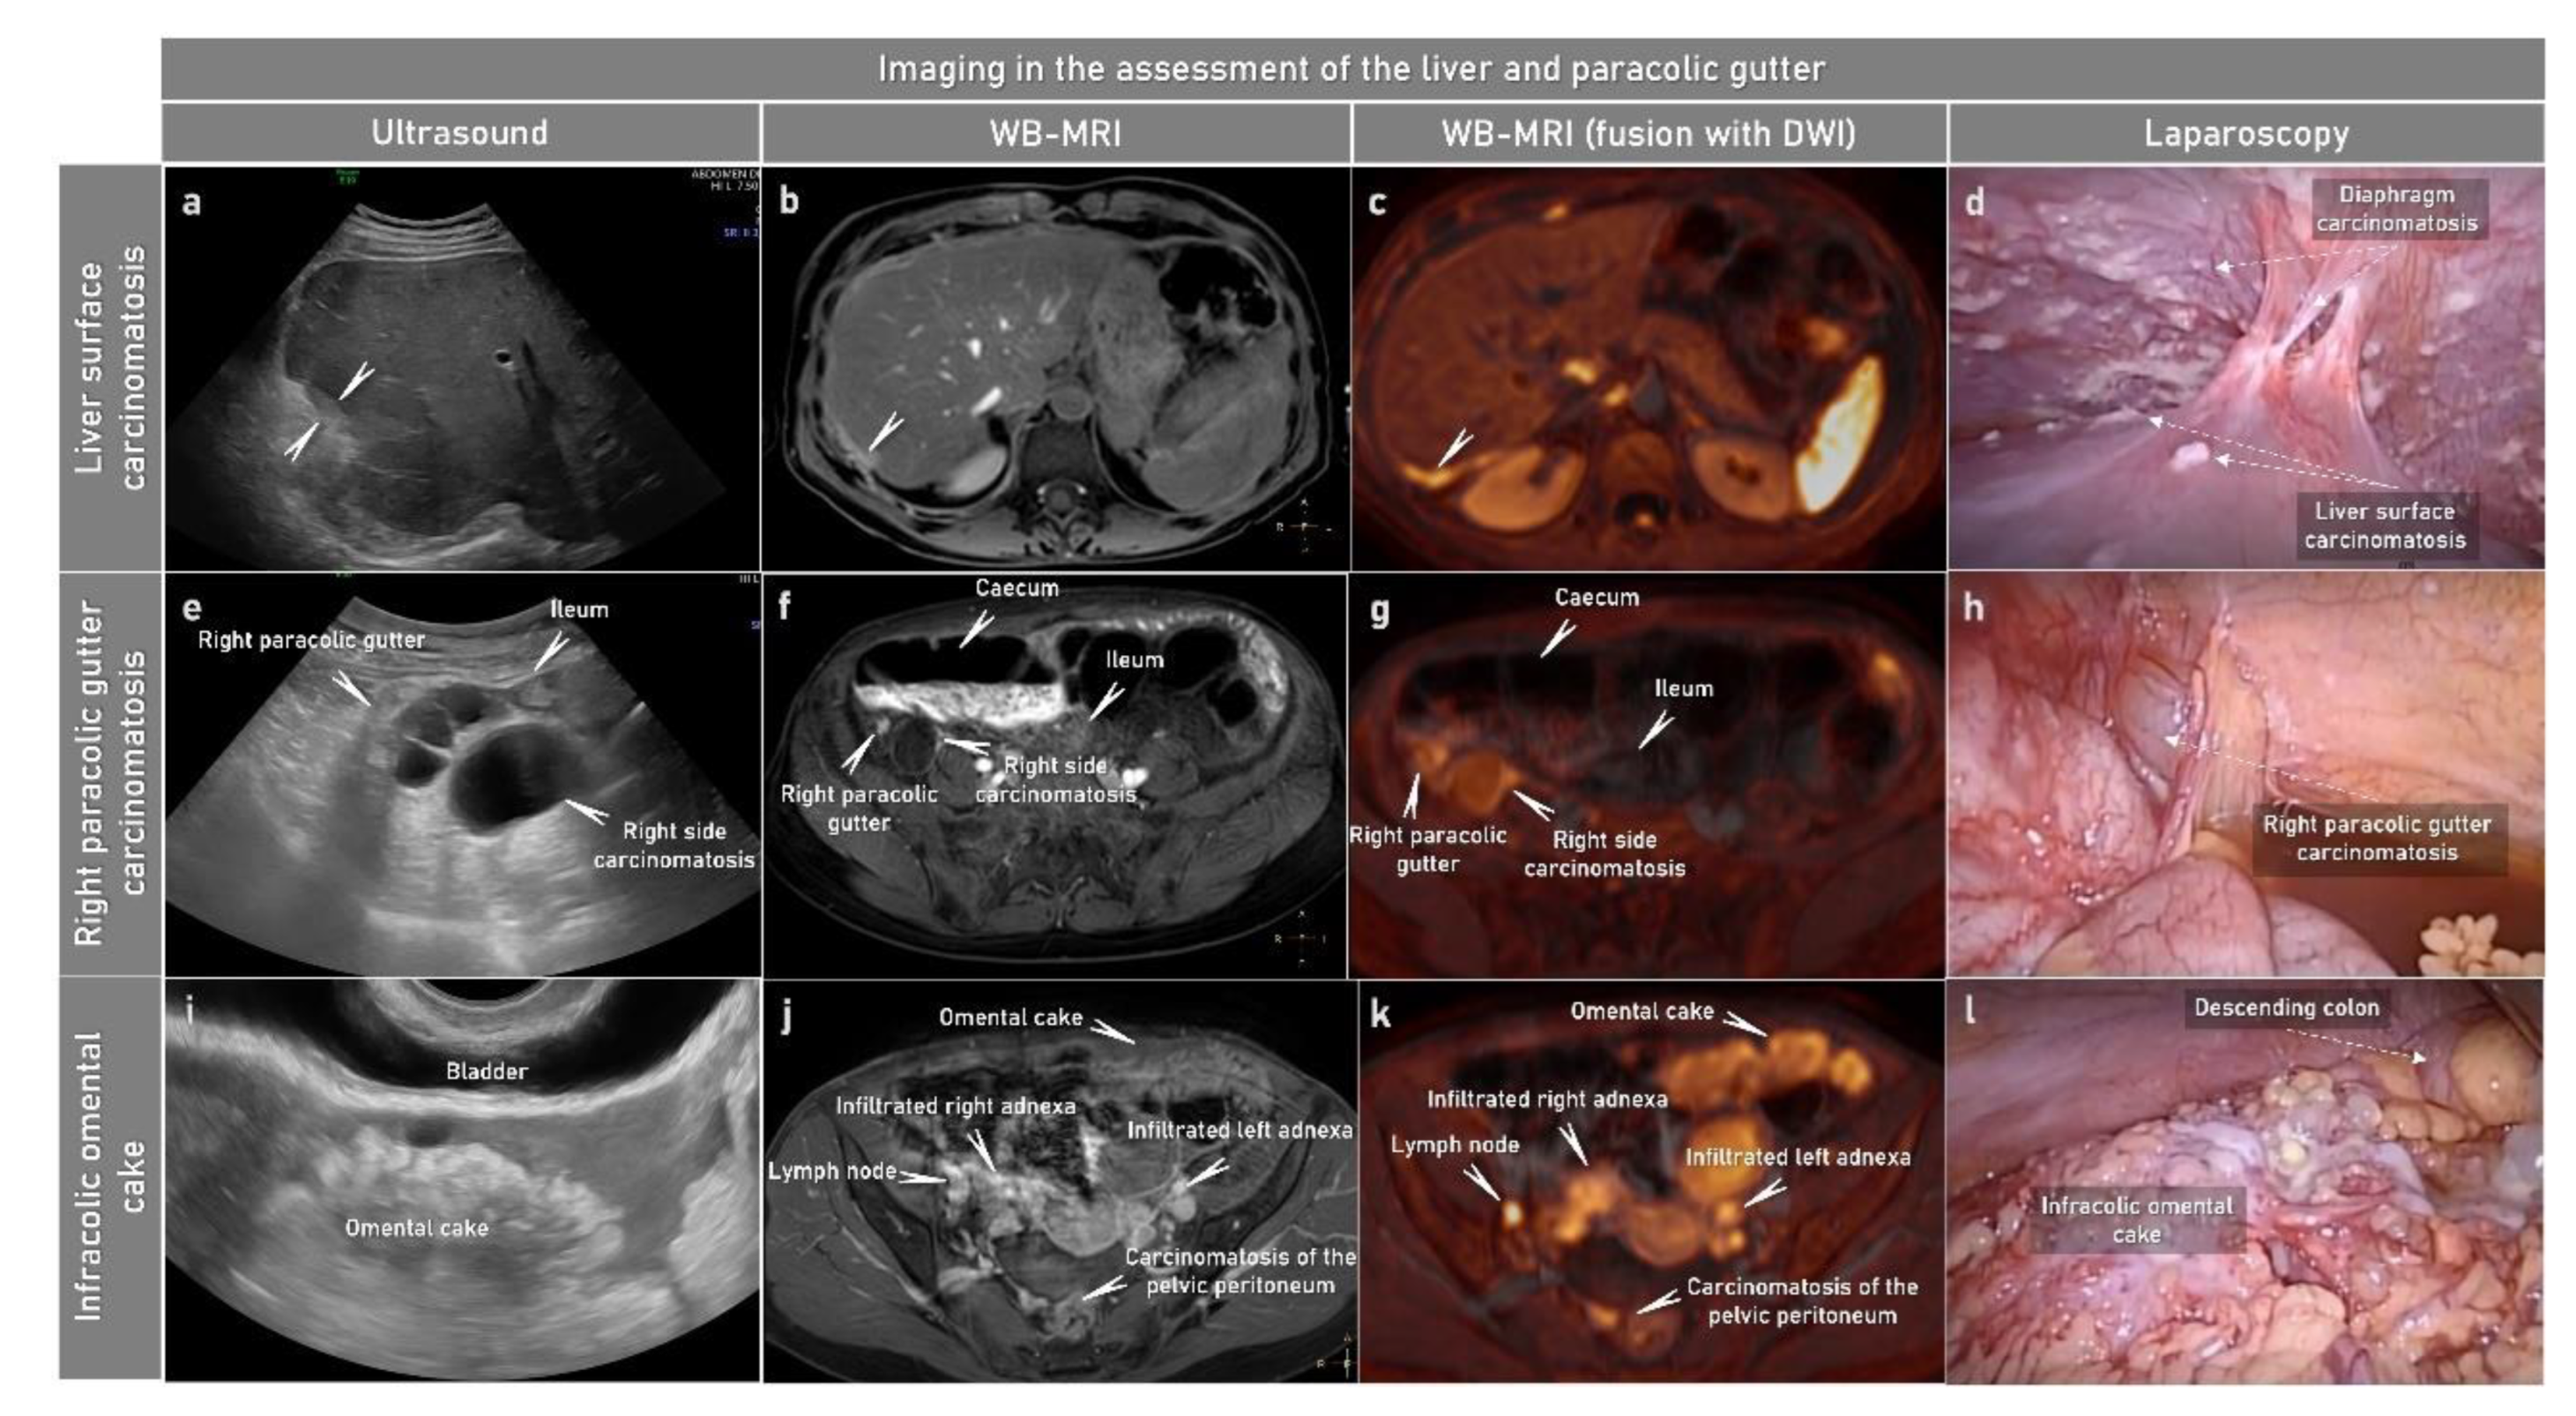

2.3.1. Ultrasound

2.3.2. Computed Tomography

2.3.3. Magnetic Resonance Imaging

- Nougaret, S.; Addley, H.C.; Colombo, P.E.; Fujii, S.; Al Sharif, S.S.; Tirumani, S.H.; Jardon, K.; Sala, E.; Reinhold, C. Ovarian carcinomatosis: How the radiologist can help plan the surgical approach. Radiographics 2012, 32, 1775–1800; discussion 1800-3. [Google Scholar] [CrossRef]